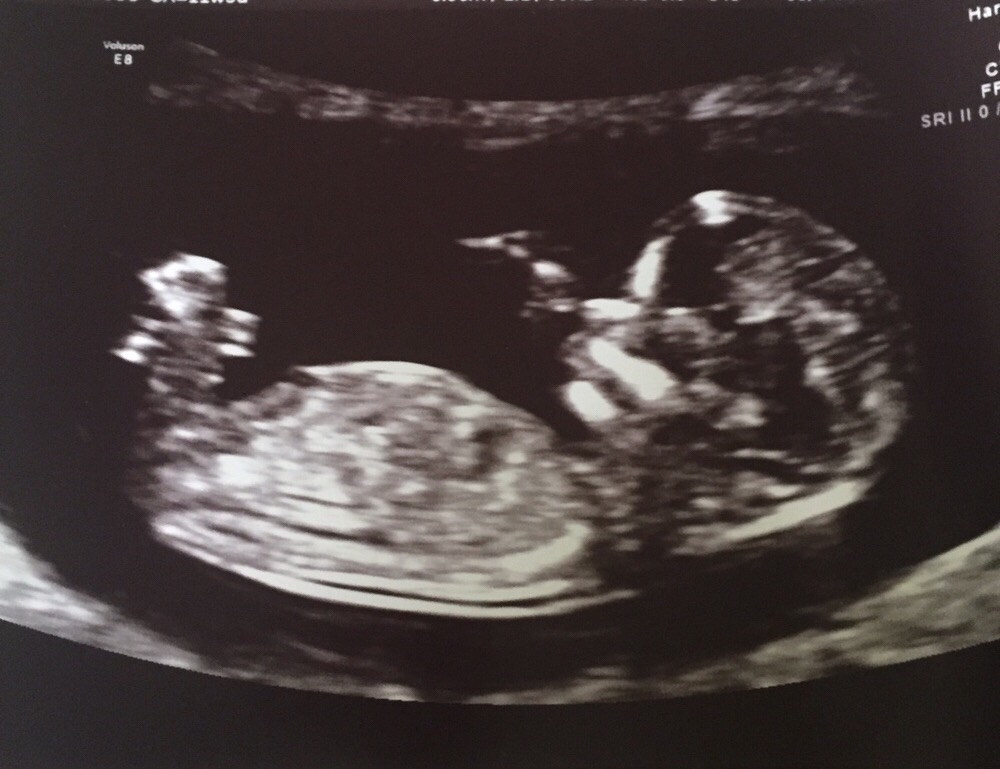

Second ultrasound

Hb 156,